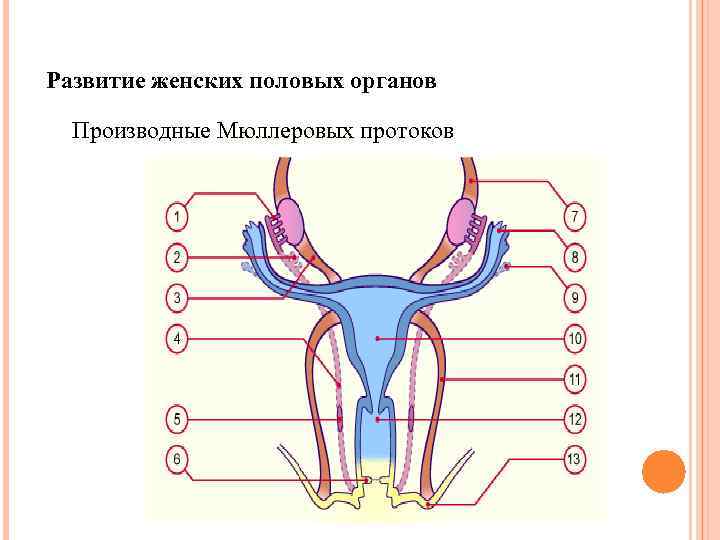

Развитие женских половых органов Производные Мюллеровых протоков Мюллеровых

Развитие женских половых органов Производные Мюллеровых протоков Мюллеровых